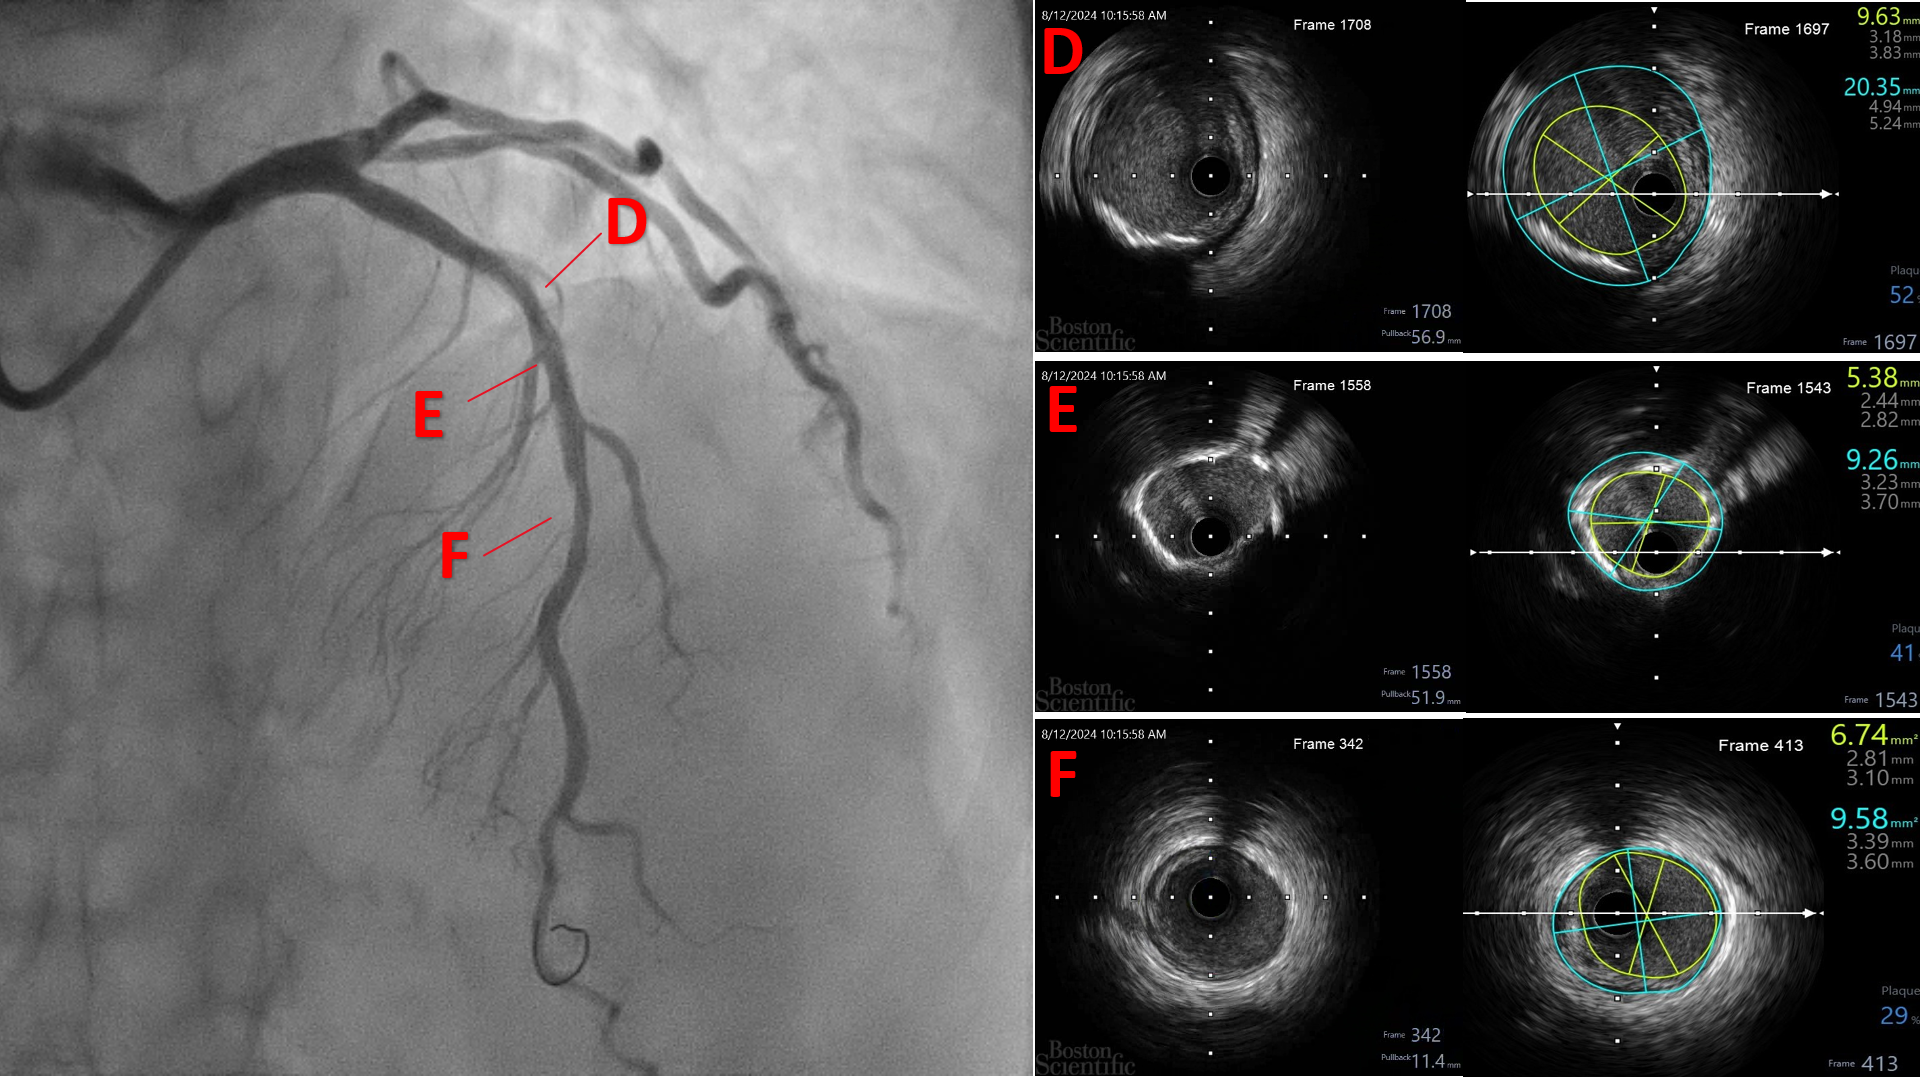

The patient was electively admitted for diagnostic coronary angiography on August 12, 2024, which revealed single-vessel disease (SVD) with 95% stenosis in the proximal to mid left anterior descending (LAD) artery. The LAD lesion is tight and calcified. His Left circumflex vessel and right coronary vessel are normal. We proceeded with percutaneous coronary intervention (PCI) to the LAD with DCB only strategy.

The procedure was performed using a 7 Fr right radial approach. A total of 6000 units of intracoronary heparin and 300 mg of oral clopidogrel were administered. The left coronary system was engaged with a 7 Fr extra-backup (EBU) 3.5 mm guiding catheter, and the lesion was successfully crossed with a Run-through floppy wire extending to the distal LAD. Pre-dilation was performed with a 2.0 mm x 15 mm Genoss balloon, inflated to 16 atm. Intravascular ultrasound (IVUS) imaging revealed 360-degree superficial calcium at the tight LAD lesion, a vessel diameter under 3.5 mm, and a calcium score of 2. The mid-LAD measured 3.0 mm and the proximal LAD measured 4.0 mm. Pre-dilation was performed in the mid-LAD using a 3.0 mm x 16 mm Genoss non-compliant (NC) balloon, and in the proximal LAD with a 3.5 mm x 20 mm NC Emerge balloon, both inflated to 16 atm. Post-pre-dilation IVUS imaging showed cracking of the superficial calcium with vessel expansion to 3.0 mm. Subsequently, drug-coated balloon (DCB) angioplasty was performed with a 3.0 mm x 30 mm Magic Touch DCB in the mid-LAD and a 3.5 mm x 35 mm Magic Touch DCB in the proximal LAD. Final angiography demonstrated a non-flow-limiting Type A dissection with less than 30% recoil, and the procedure was successfully concluded.